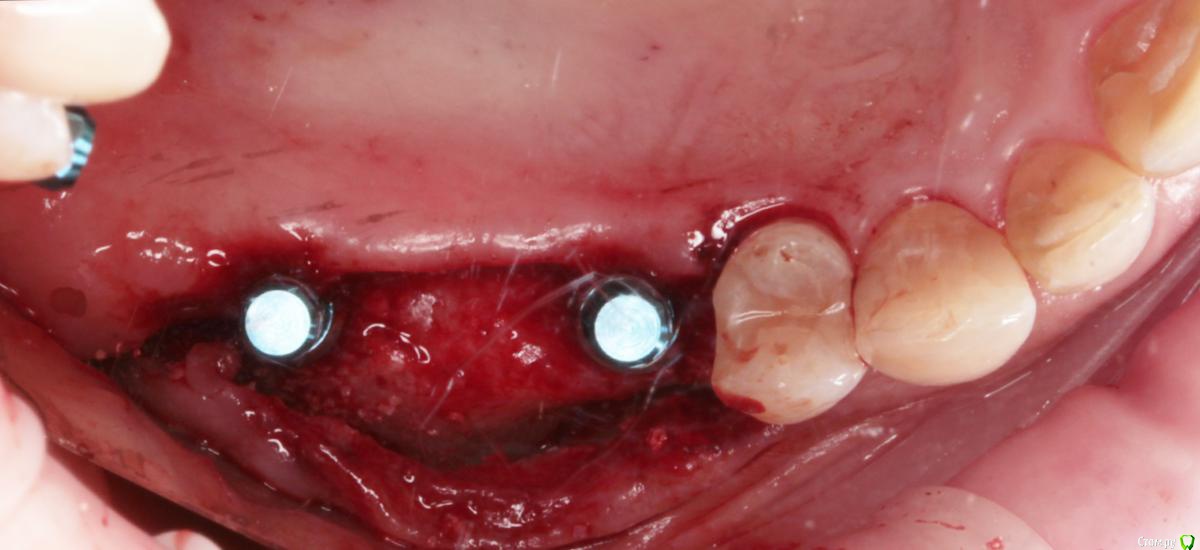

1) имплантация в позиции 15,17 з с закрытым синусом и незначительной НКР

2) коррекция слизистой в области 1-го сегм